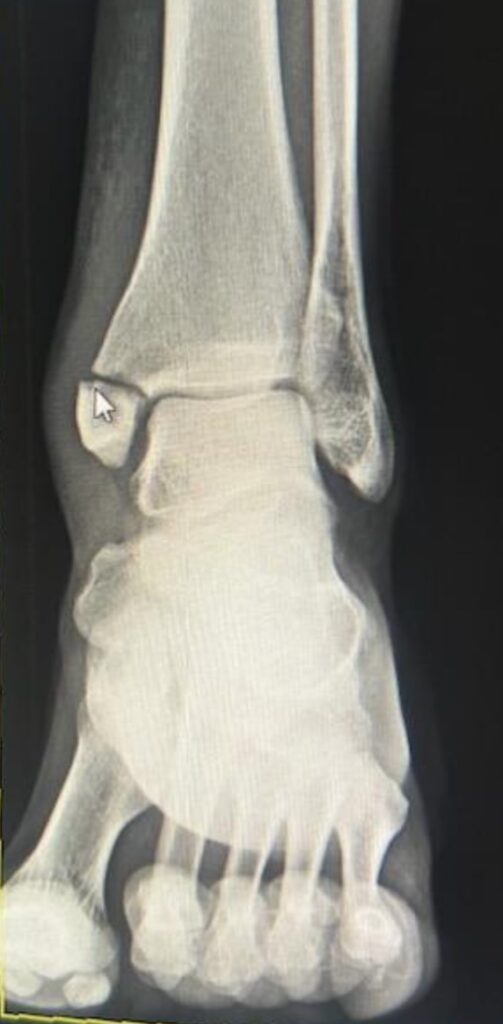

Tibia fractures can be season ending if surgery is required. When the fracture is low on the ankle and especially when it extends into the joint it needs screws and/or plates to fixate it to allow for proper healing. Fractures like the one seen below (this is not an x-ray of Rashaad Penny) are unstable and require surgery.